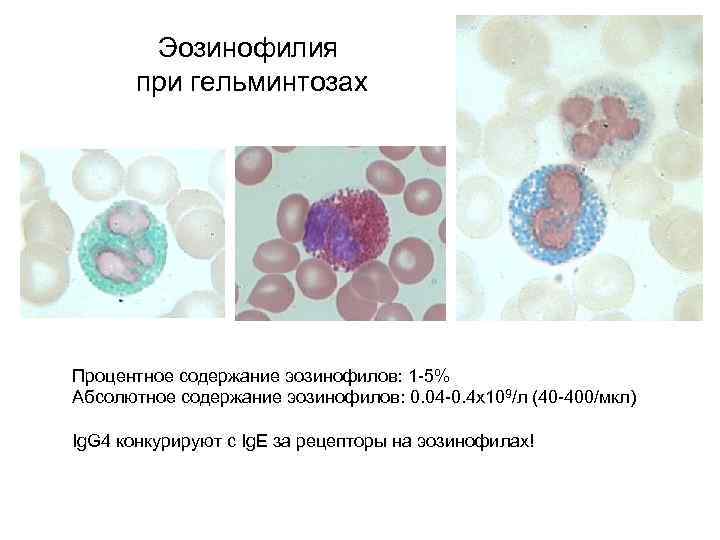

Эозинофилия при гельминтозах Процентное содержание эозинофилов: 1 -5% Абсолютное содержание эозинофилов: 0. 04 -0. 4 x 109/л (40 -400/мкл) Ig. G 4 конкурируют с Ig. E за рецепторы на эозинофилах!